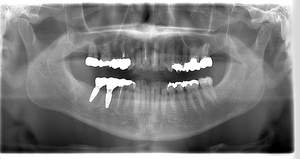

レントゲン写真

- Befor

- After

| 年齢 | 50代・男性 |

| 主訴 | 左下7番 |

| 治療内容 | 右下7番インプラント埋入 |

| 治療費 | 合計:572,000円 診断料:55,000円 埋入料:165,000円 サージカルガイド:55,000円 静脈内鎮静麻酔:77,000円 仮歯:55,000円 上部構造(フルジルコニア):165,000円 (2023年1月現在) |

| 治療期間 | 約8ヶ月 |

| 治療方針 | 骨が十分にあるため、骨造成をすることなく埋入した。かみ合わせが強いので、負荷がかからないよう、夜寝るときにマウスピースをつけるよう指示をした。 |

| 担当者所見 | 左下6番7番のインプラントは他院で埋入しており、右下7番は抜歯したままで、かみ合わせの歯が落ちてきてしまうのでインプラントを埋入しました。 |